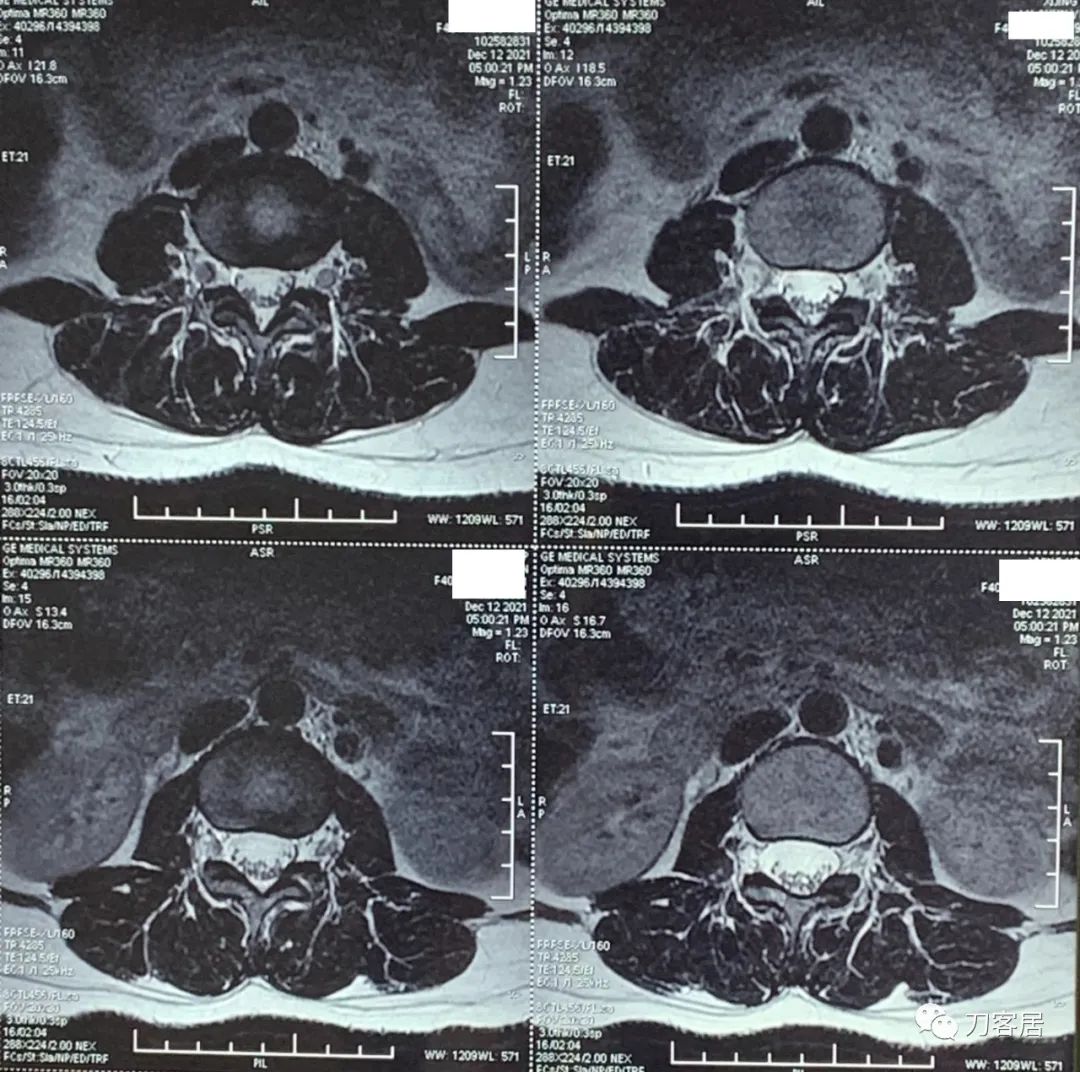

自带腰椎MRI检查未见异常。腰椎X线片提示左侧腰5横突肥大。自带外院骨密度检查结果正常。

20211212西京医院腰椎MRI.